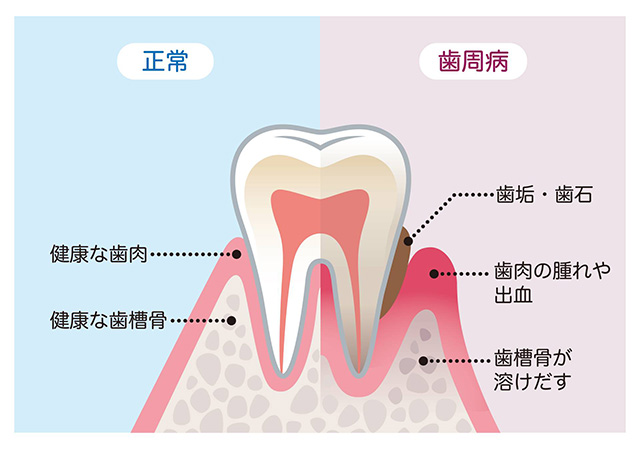

歯周病は、歯と歯ぐきのすき間(歯周ポケット)に細菌が入り込み、歯ぐきに炎症を起こしたり、歯を支える骨(歯槽骨)を溶かす病気です。

初期の「歯肉炎」では歯ぐきの炎症だけですが、進行すると「歯周炎(歯槽膿漏)」になり、歯のぐらつきや腫れ、最悪の場合は歯を失ってしまうこともあります。

主な原因は、歯と歯ぐきの間にたまるプラーク(歯垢)です。

プラークは細菌のかたまりで、放置すると固くなって「歯石」となり、細菌の温床になります。

歯ぐきは薄いピンク色で引き締まっており、歯と歯ぐきのすき間(歯周ポケット)もなく、ブラッシングしても出血しません。